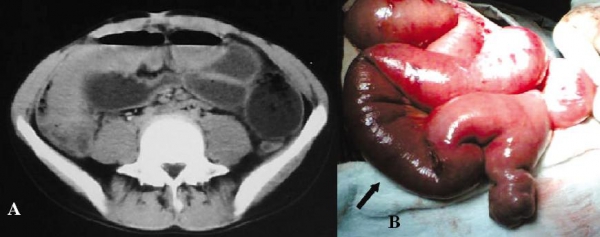

Hình 17: Hoại tử hồi tràng do chui vào thòng lòng được tạo bởi đầu tận cùng túi thừa Meckel dính với măt lưng mạc treo ở bệnh nhân nam 32 tuổi. A, CT quai ruột non dãn lớn, đoạn hồi – manh tràng xẹp nên nghi ngờ tắc ở hồi tràng. B, phẫu thuật: túi thừa Meckel và đoạn hồi tràng bị hoại tử. (Oguzhan KARATEPE. Cem DURAL et al (2008). Rare Complication of Meckel’s Diverticulum: Loop Formation of Diverticulum. Turk J Med Sci; 38 (1): 92.)

Hình 17C: Hình vẽ mô tả quai ruột non chui vào thòng lòng của túi thừa Meckel dính đầu tận cùng với mạc treo.